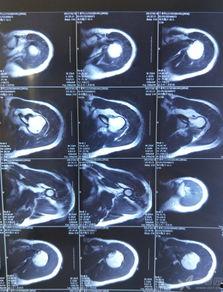

首先,得先了解一下肩关节半脱位。简单来说,就是肩关节的骨头和关节盂之间发生了轻微的错位。这种情况可能是因为肩部受到外力撞击、过度拉伸或者姿势不当等原因造成的。虽然听起来有点吓人,但其实很多情况下,肩关节半脱位是可以自行恢复的。